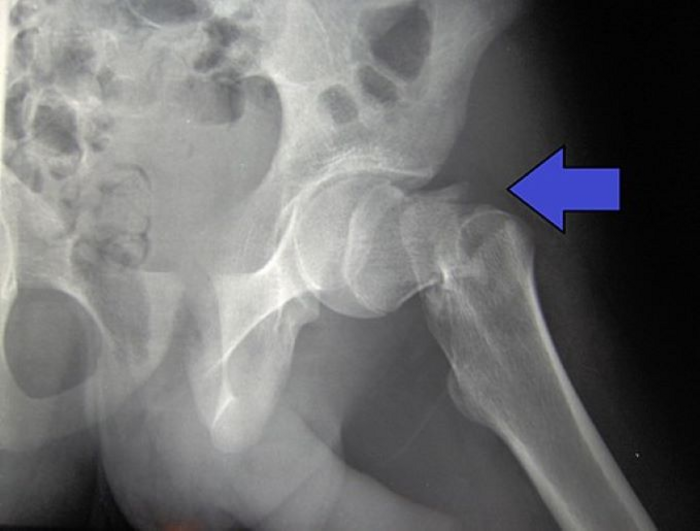

The research could in future be applied to improve balance in older people and help reduce falls, this could be applied through either wearable devices or with a daily session of stimulation. Hip fractures alone account for 1.8 million hospital bed days and £1.1 billion in hospital costs every year, excluding the high cost of social care.